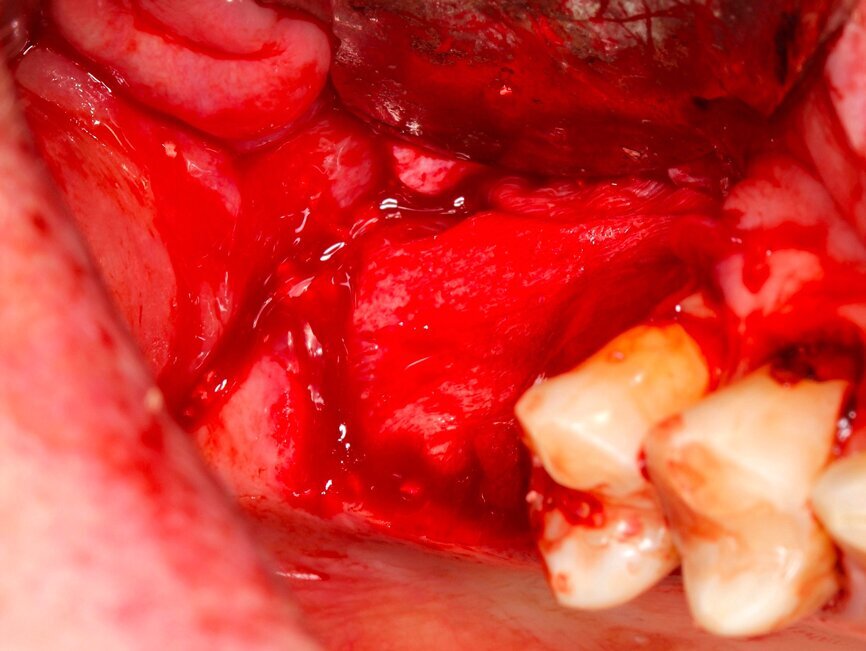

Fig. 13 Figura 13

1. Anestesia infiltrativa vestibular y lingual o palatina de la zona a intervenir.

2. Incisión paracrestal 2 mm hacia palatino con hoja de bisturí 15C y descargas liberadoras mesial y distal para una correcta visión del campo quirúrgico.

Fig. 14 Figura 14

1. Elevación del colgajo mucoperióstico a espesor total con periostotomo exponiendo el defecto en su totalidad.

2. Determinación de las dimensiones del injerto.